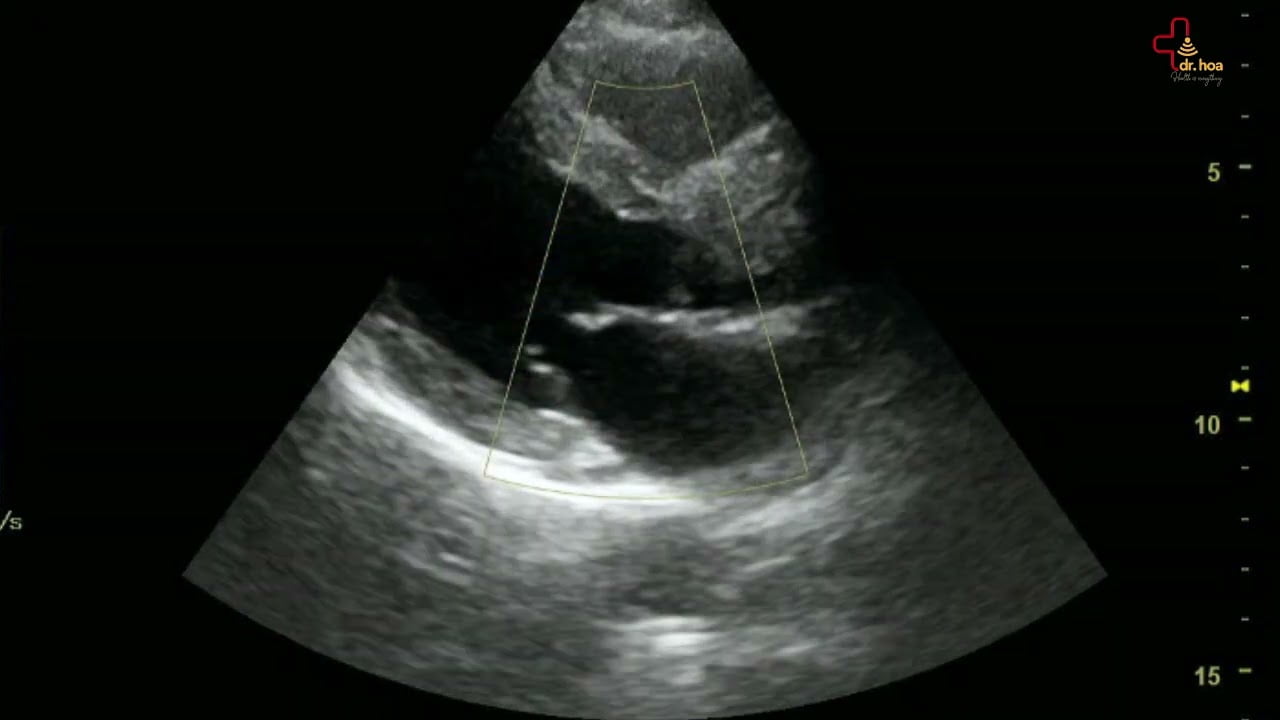

Sieu am Q7 xin gioi thieu case sieu am bung tong quat

Siêu âm Q7 xin giới thiệu case #siêu_âm_bụng_tổng_quát.

Long ruot